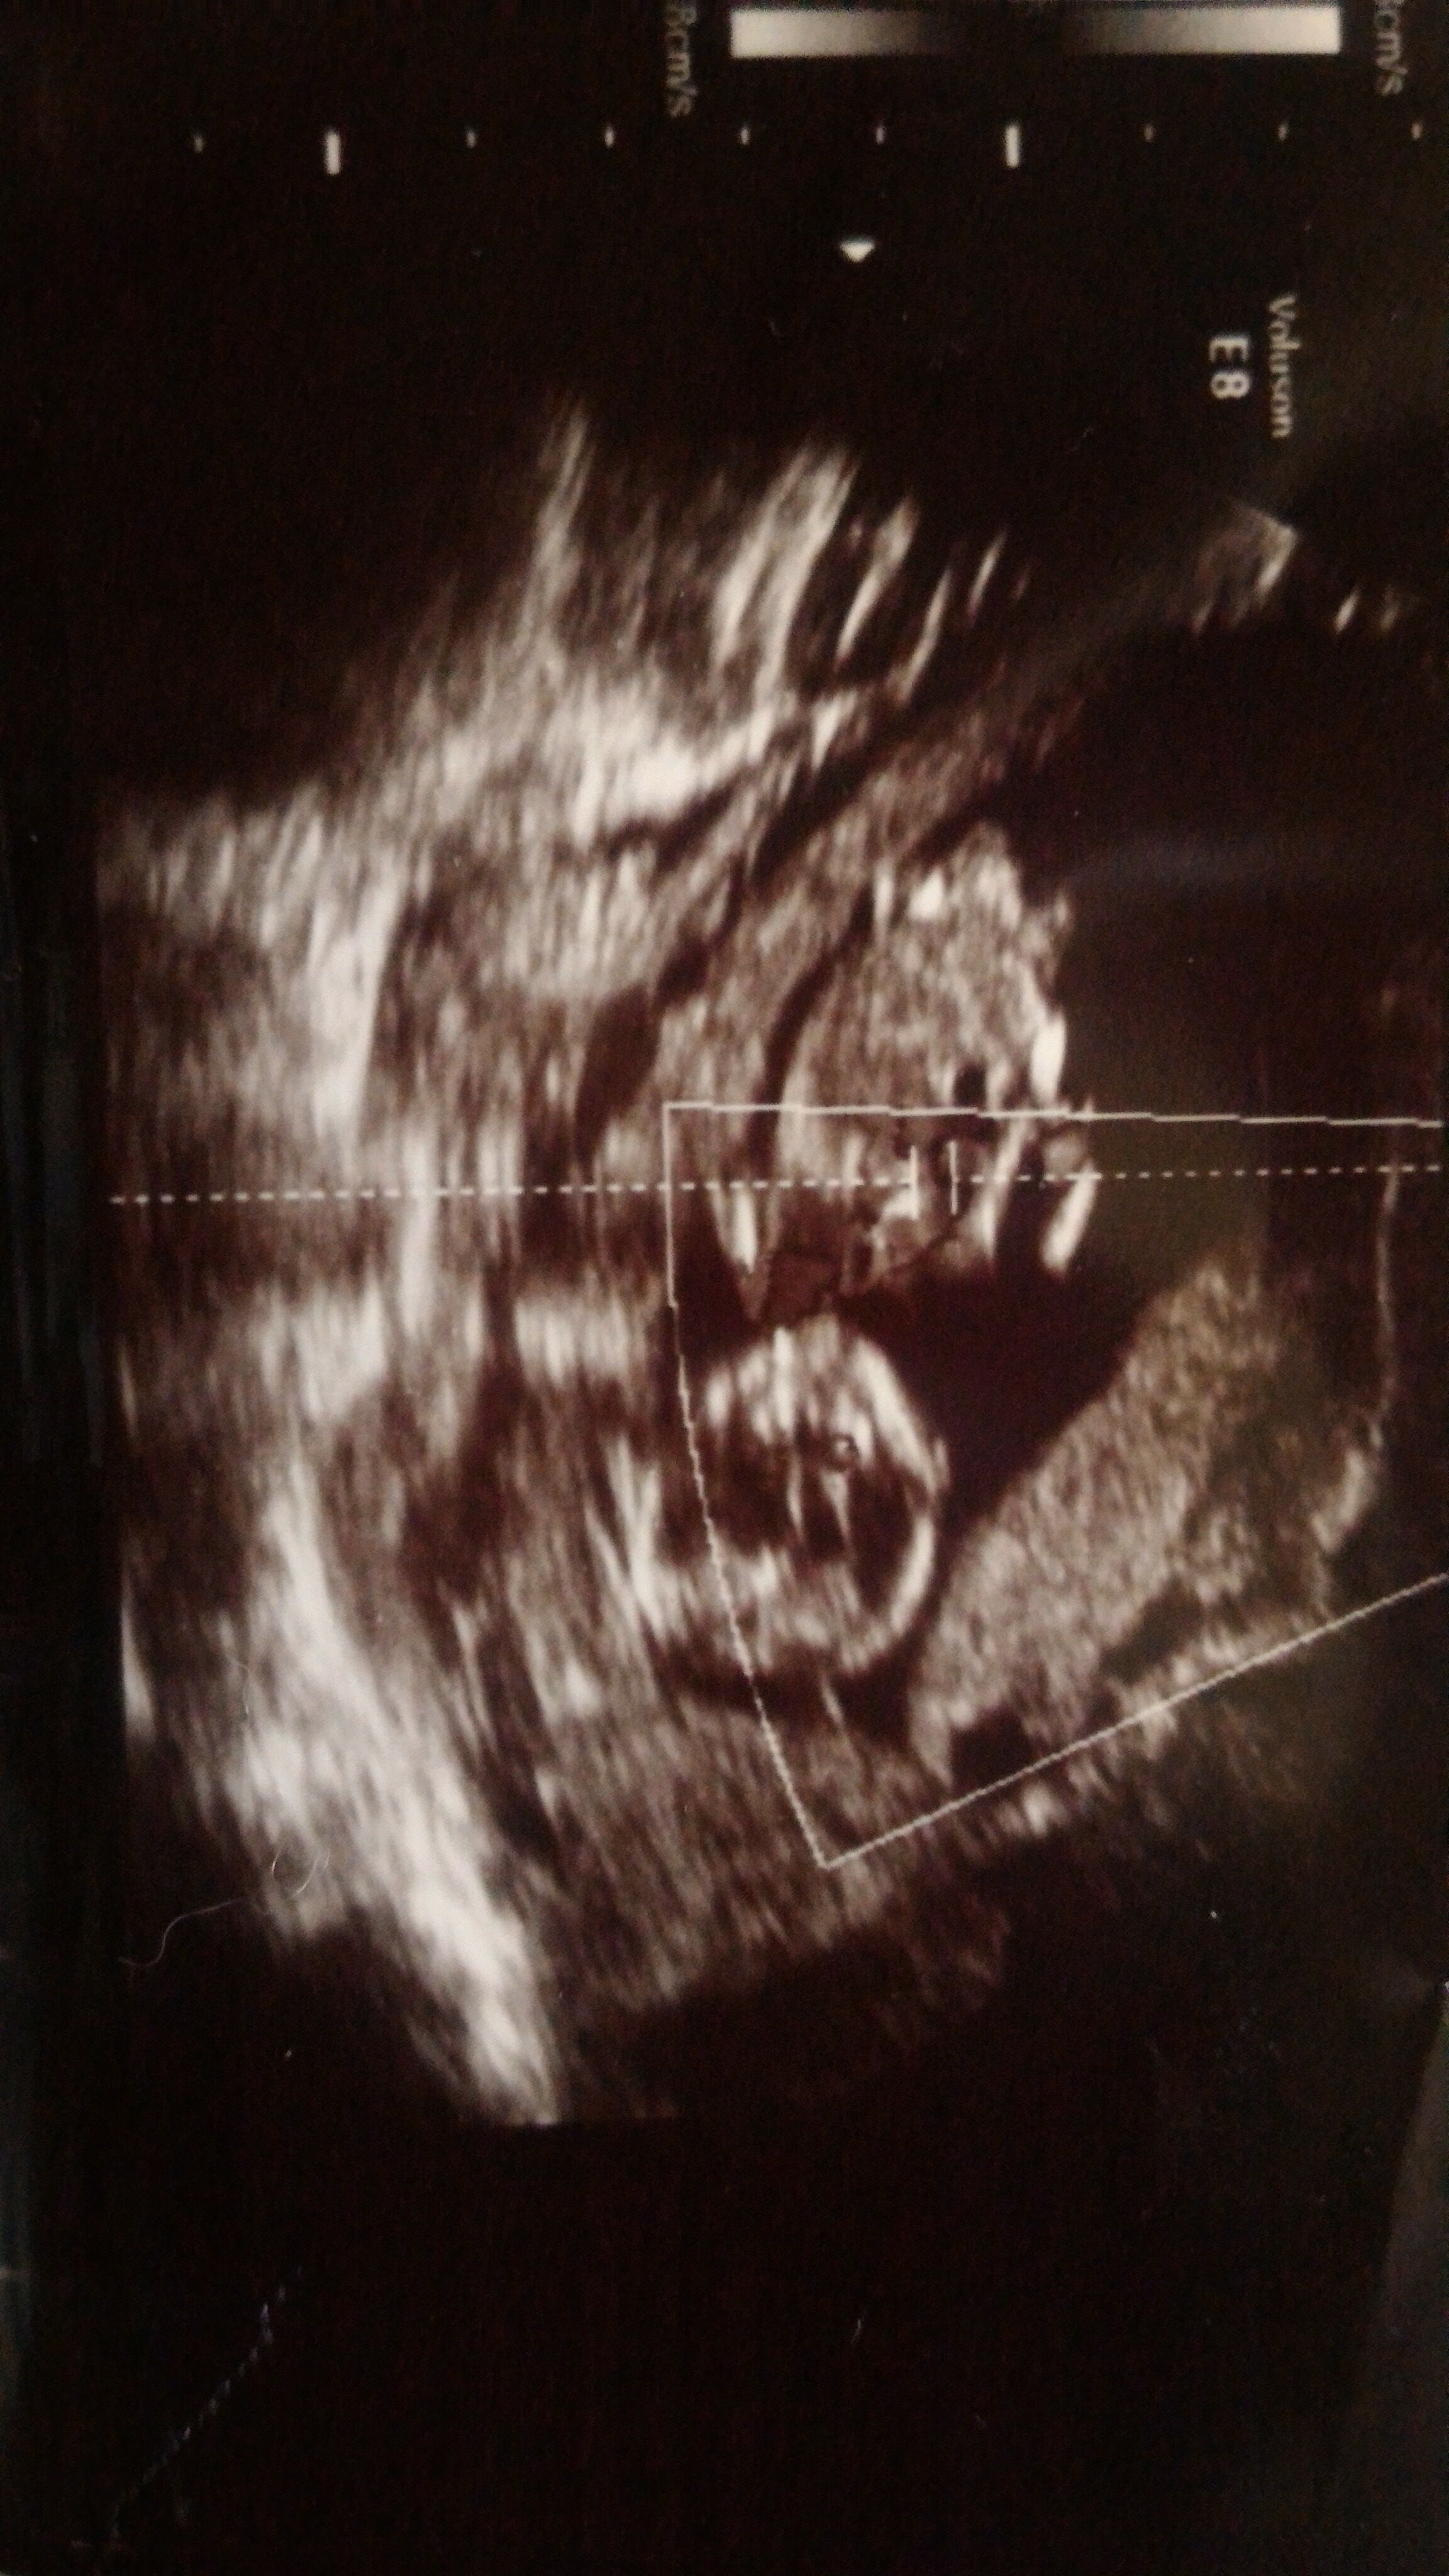

AlyaYahya61 Yeni Üye Üye 27 Şubat 2017 #199 Merhabalar Rica etsem arkadaşım için yorumlayabilirmisiniz?